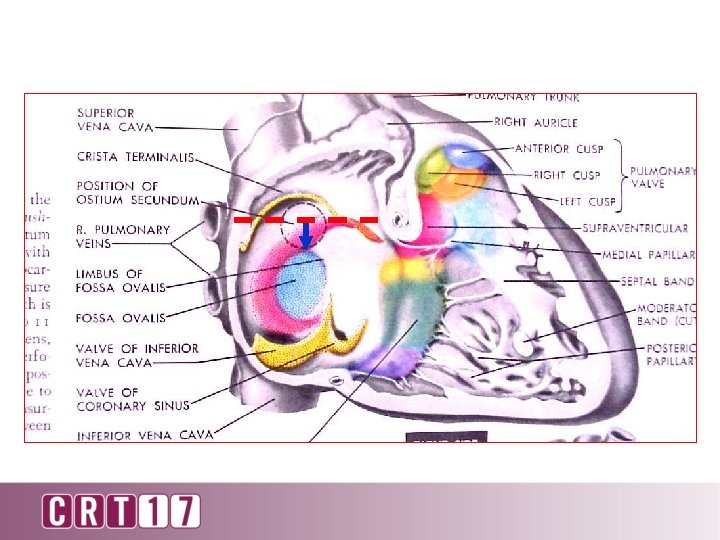

Puncture? No

Puncture? No

90 o lateral

90 degree lateral